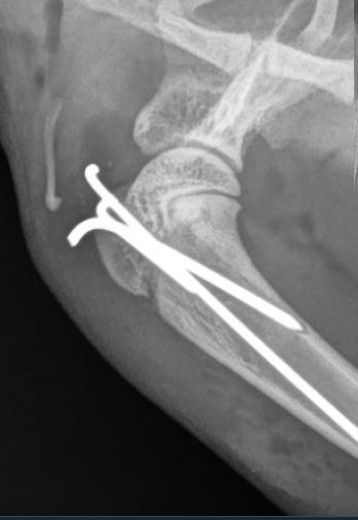

Die Fraktur muss chirurgisch versorgt werden, weshalb wir Zelda an eine nahegelegene chirurgische Überweisungspraxis überweisen. Dort wird der Bruch operativ mittels 3 Nägeln versorgt. Die postoperativen Röntgen zeigen eine gute Reposition (Wiederherstellen der normalen Anatomie des Knochens). Nun muss Zelda leider noch einige Wochen in ihrer Bewegung eingeschränkt werden (Boxenruhe), damit der Bruch gut heilen kann - glücklicherweise schreitet die Knochenheilung in diesem jungen Alter aber schnell voran.

Frakturen bei Jungtieren finden häufig in diesen weniger stabilen Epiphysenfugen statt. Zur Reparatur werden meist Marknägel verwendet, welche in einer verkeilenden Art in den Knochen gebohrt werden. So kann der Knochen entlang der Nägel weiter wachsen; ausserdem ist bei dieser Methode zur Fixation nicht auf beiden Seiten der Fraktur ein längeres Knochenstück nötig (wie zum Beispiel bei einer Verplattung). Falls die Nägel nicht stören, können sie belassen werden und werden zT vom wachsenden Knochen richtiggehend "überwuchert".